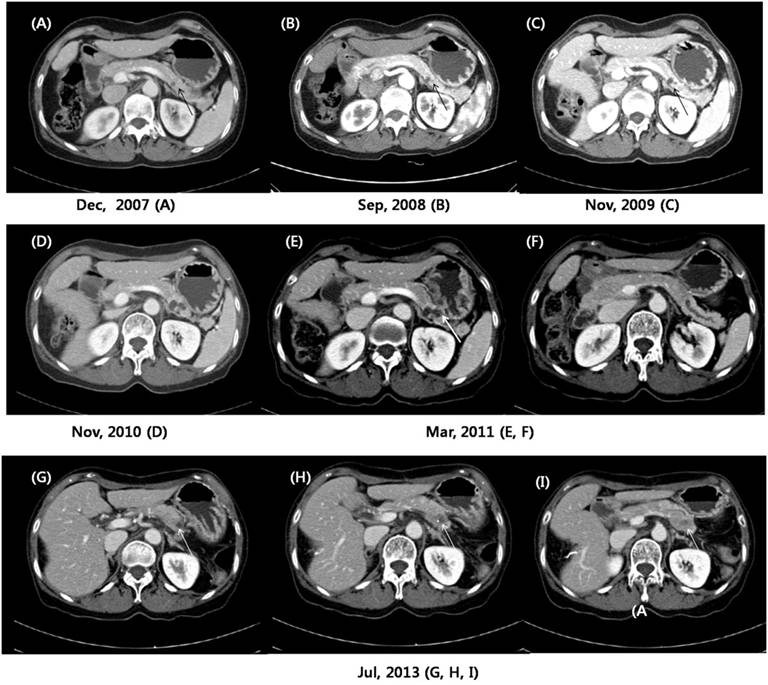

A 69-year-old woman was admitted to operate a pancreatic mass. She had a history of hepatocellular carcinoma, and underwent hepatectomy in 2003, therefore followed regularly by abdomen CT scan. A small benign looking cyst appeared in the CT scan on 2007, and remained unchangeable until 2009 (Figure 1-A, B, C). However, it grew slowly and in March 2011, a pancreatic mass located at the tail became larger (up to 2cm sized) and caused prominent dilatation of the pancreatic duct, suggesting combined type IPMN (Figure 1-D, E, F). She was taken distal pancreatectomy with splenectomy in May 2011. Pathologically, it was a 1.5cm sized IPMN with high grade dysplasia. The resection margin was free of tumor and the distance was 0.5cm.

Figure 1. (A-F) Serial change of the IPMN of the pancreas; (G-I) A-3.5 cm sized recurrent mass in the remnant pancreas. |

On the follow up CT scan taken 26 month after operation, 3.5cm sized mass in the distal remnant pancreas appeared (Figure 1-G, H, I). It was suspicious of recurrence of IPMN. She was operated to remove remnant body of pancreas. It was a multilobulated ill-demarcated whitish mass, measuring 3.4x3.2x2.6cm. It was 5cm apart from proximal pancreatic resection margin. It was an IPMN with an associated a poorly differentiated adenocarcinoma. Depth of invasion was peripancreatic tissue and lymph node metastasis was not detected. The patient recovered without complication.